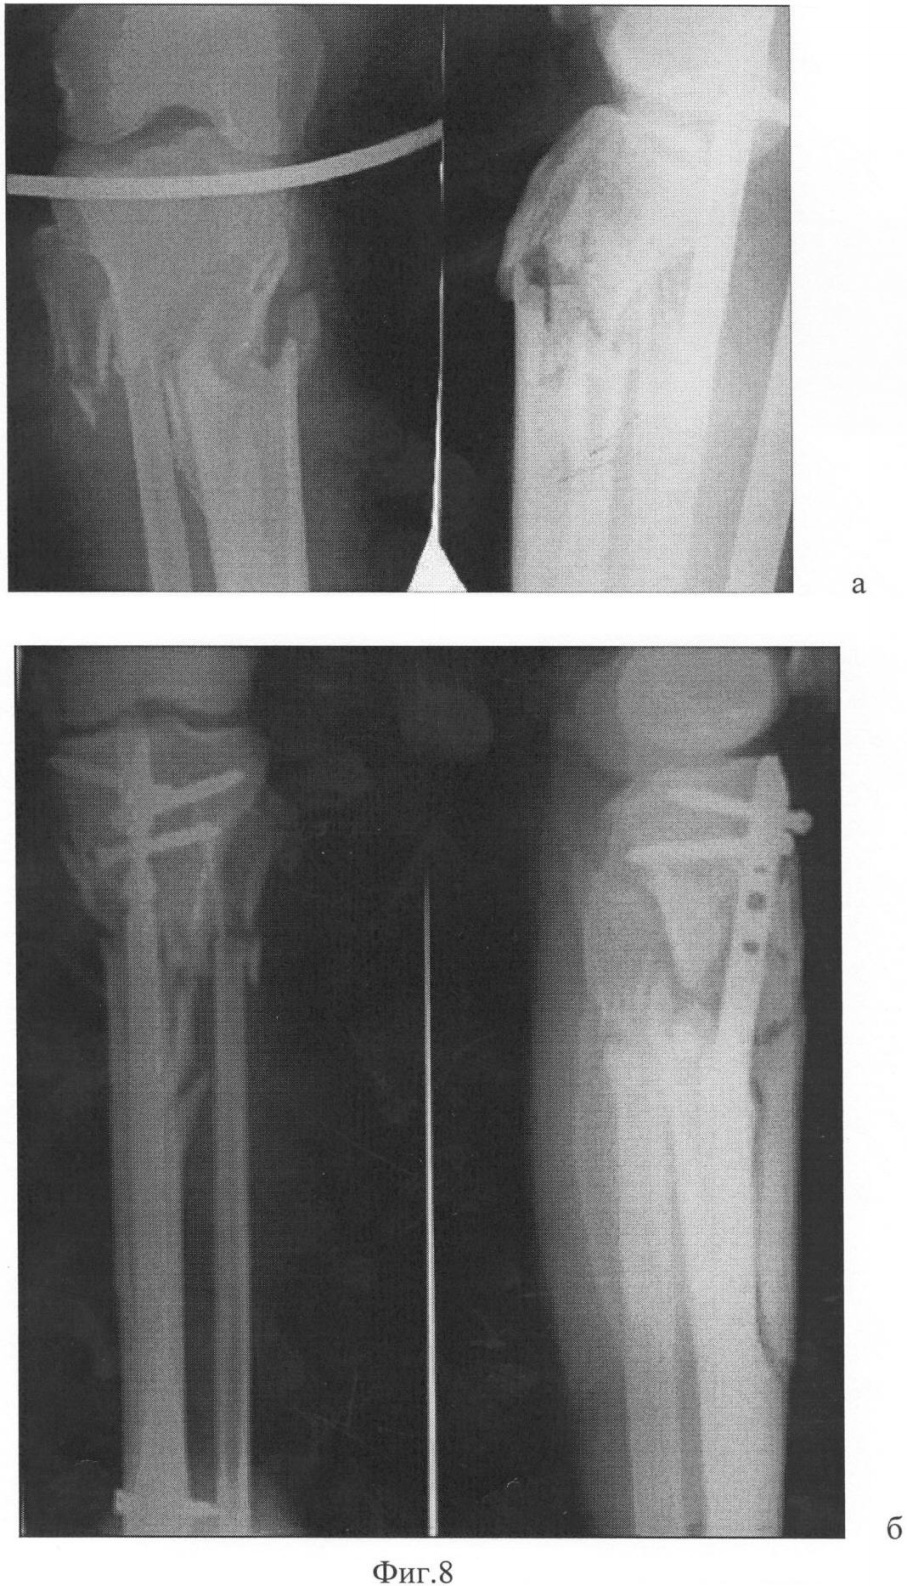

2. Высокий проксимальный перелом большеберцовой кости.

На Фиг.8 – рентгенологическая картина с введенными отклоняющими спицами: а – вид спереди; б – вид сбоку.